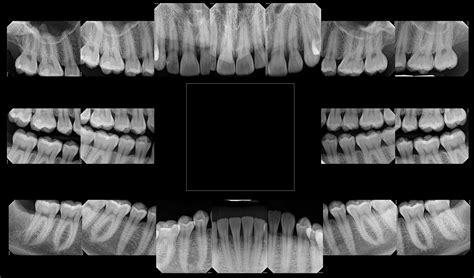

Panoramic xray image of teeth and mouth with wisdom teeth Parkview

Panoramic xray image of teeth and mouth with wisdom teeth Parkview from fountainhillsdentist.com

Now, let's delve deeper into the importance of x-rays in dental care. X-rays are a valuable tool that dentists use to assess your oral health. They provide a detailed view of your teeth, jawbone, and surrounding tissues, helping dentists identify various dental conditions. X-rays can detect cavities between teeth, impacted wisdom teeth, jawbone infections, gum disease, and even oral cancer.

Now let's dive deeper into the topic of dental x-rays. There are two main types of dental x-rays: intraoral and extraoral. Intraoral x-rays are the most common and provide a detailed view of the teeth and surrounding structures. Extraoral x-rays focus on the jaw and skull, providing information about the positioning and alignment of the teeth.

Digital x-rays have also become more prevalent in recent years. They offer numerous advantages over traditional film x-rays, including reduced radiation exposure, immediate results, and the ability to store and share images electronically.

During a dental x-ray procedure, a small sensor or film is placed inside your mouth to capture the images. The x-ray machine is positioned outside your mouth, and the dentist or dental assistant will take the necessary precautions to ensure your safety and comfort during the procedure.